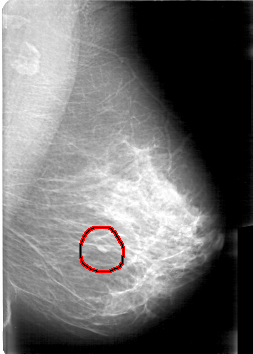

D_4065_1.LEFT_MLO

FILE: D_4065_1.LEFT_CC.OVERLAY

TOTAL_ABNORMALITIES 1

ABNORMALITY 1

LESION_TYPE MASS SHAPE OVAL MARGINS OBSCURED

ASSESSMENT 0

SUBTLETY 4

PATHOLOGY BENIGN

TOTAL_OUTLINES 1

BOUNDARY